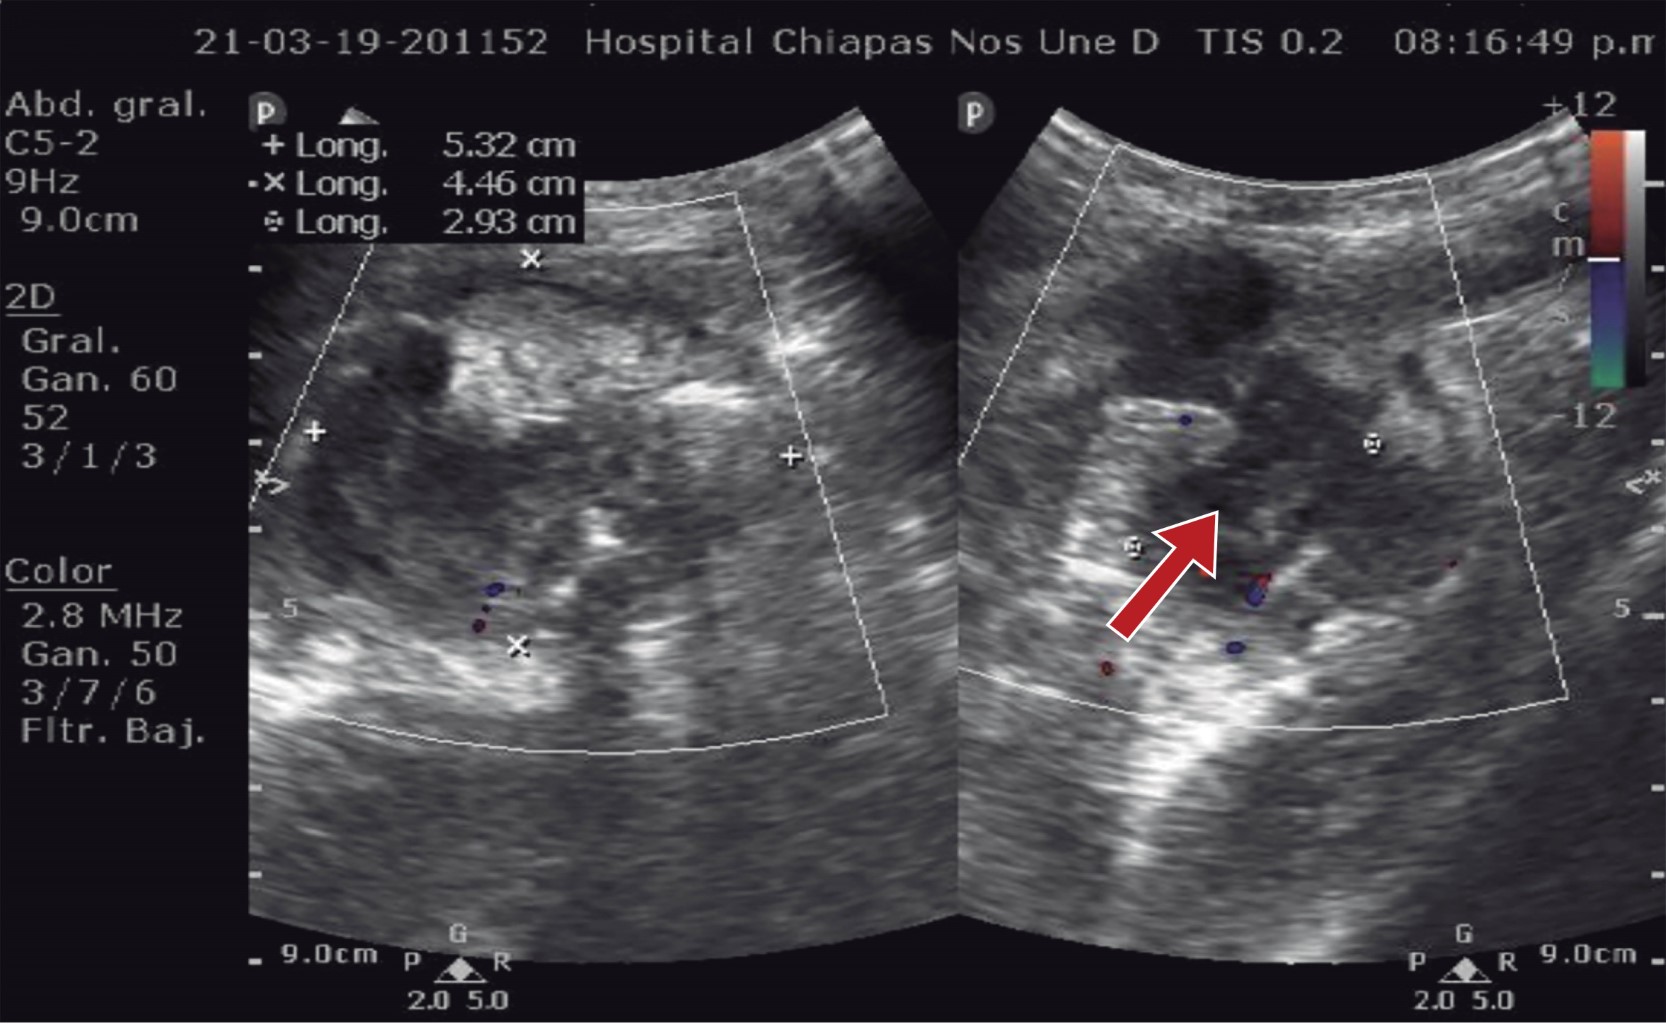

We report the case of a nine-year-old male with a history of having undergone surgery for acute appendicitis two and a half years before his current condition, which began 10 days before his admission and was characterized by generalized abdominal pain and vomiting on two occasions with gastro alimentary characteristics, managed by a physician with unspecified analgesics and without improvement. He continued with abdominal pain, predominantly in the right lower quadrant, accompanied by nausea and vomiting. For this reason, he went to the Emergency Department of the hospital, where the patient was found with pain in the right lower quadrant, in the trigger position, and with data of peritoneal irritation. Laboratory tests were requested, reporting a hemoglobin level of 13.0 mg/dl, hematocrit of 38.2%, 15.15 × 109 white blood cells, and 76.4% neutrophils. The plain abdominal X-ray showed a fixed loop image in the right iliac fossa (Figure 1). An abdominal ultrasound was requested, which reported a collection of 5 × 4 cm (Figure 2), so the General Surgery Service was consulted since there was no pediatric surgeon on shift; 24 hours after admission, the patient was evaluated by surgery, finding the patient with discrete voluntary resistance in the right lower quadrant and peritoneal irritation. An abdominal MRI was requested to determine the probable etiology of the collection, which reported an amorphous collection in the right iliac fossa, with irregular and well-defined borders, measuring 5.1 × 4.3 × 4.9 cm in its longitudinal and transverse anteroposterior diameters, respectively, compatible with an abscess in the right iliac fossa.

Figure 2